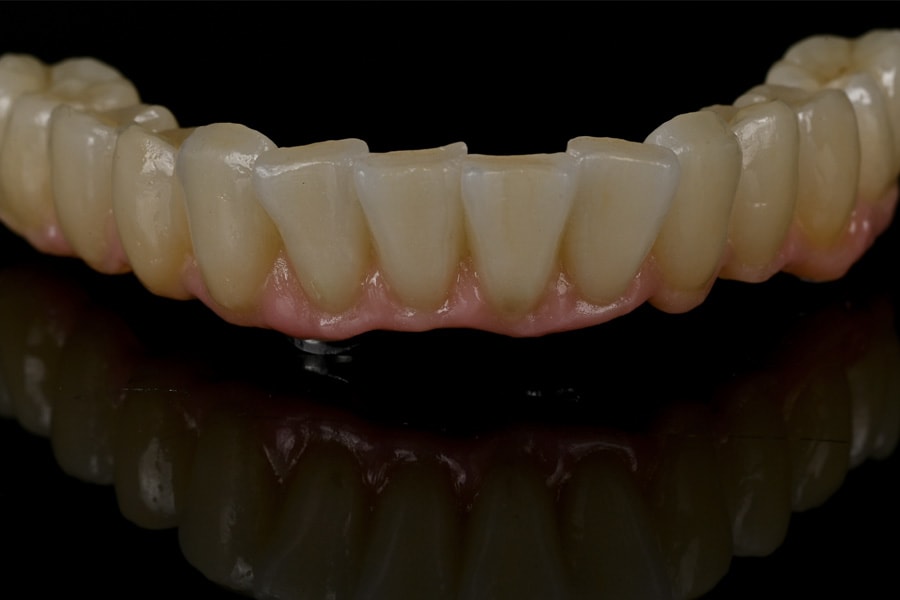

CAD/CAM-milled polymethyl methacrylate (PMMA) provisionals were fabricated in advance, with screw-access and pick-up channels prepared (Figure 16 and Figure 17). These provisionals replicated the digital smile design and occlusal blueprint, enabling immediate esthetic and functional rehabilitation.

During surgery, flapless osteotomies were prepared under guided conditions. All implants achieved insertion torque values sufficient for immediate loading. Multi-unit abutments were connected, and the PMMA provisionals were relined intraorally, ensuring passive seating. Occlusion was carefully adjusted to light centric contacts and shallow lateral guidance, minimizing overload during early osseointegration (Figure 18 and Figure 19).